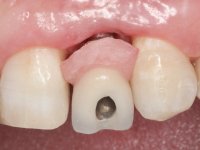

• Placement of an implant at the tooth site 2.2. Rehabilitation of the implant with a coronary and gingival component abutment. in which the screw access hole was "camouflaged" with a feldspathic veneer.

Treatment began with re-preparation of the cast post and core, with the purpose of placing the cervical finishing lines with an intra-sulcular location and simultaneously making a suitable temporary crown. With a very simple orthodontic treatment, the diastema was closed between the upper central incisors, and this position was stabilized with a wire placed on the palatal surface of the central, functioning as containment. Later, a slow orthodontic traction of tooth 2.2 was attempted, in order to reduce, although very slightly, the vertical bone loss in this area. At the end of the traction, tooth 2.2 was extracted and the area was provisionally rehabilitated with a composite resin crown bonded to the adjacent teeth. A dental implant was placed in the area of tooth 2.2 and the temporary crown was again bonded to resin, provisionally rehabilitating the patient during osseointegration. In tooth 1.3 a gingivectomy with an electric scalpel was performed, with the intention of raising the cervical level of 1.3 achieving greater harmony with tooth 2.3. Stabilized soft tissues were impressed using the open tray technique with putty and light addition silicones. Collection of the color of both the dental component and soft tissues was done by the ceramist in the office. In the laboratory, the impressions were transferred to plaster and gave origin to work models that were properly analyzed. It was decided to assemble a metal-ceramic abutment screwed onto the implant. This abutment was cast with a noble alloy and subsequently coated with coronary and gingival ceramics. Due to the inclination of the implant, the screwing inevitably conditioned the exit of the screw hole through the vestibular surface. In order to conceal this situation, the design of the abutment has already been conceived with the intention of accommodating on the vestibular surface the bonding of a feldspathic veneer. This abutment was tested in the mouth and adjustments were made in the gingival ceramic component. Its adaptation to the soft tissues was done in a subtractive way, with a drill, as well as additive, adding resin composed of gingival tonality.

This addition of resin would guide the ceramist in the final placement of the gingival tonality ceramic. The crown that would rehabilitate tooth 1.3 was cemented in this test session with glass ionomer cement, reinforced with composite resin. Once the laboratory work was finished on the veneer for tooth 1.2, the abutment, and the veneer for the implant, this was bonded in the mouth, after placement of the absolute insulation. The work completely satisfied the patient. For eight years, the patient had periodical check-ups, and was pleased with the treatment, but also began to show interest in an aesthetical intervention on the upper central incisors. Once the second phase of our intervention was decided, dental preparation of teeth 1.1 and 2.1 was performed for the placement of two feldspathic veneers. Particular care was taken in the distal inter-proximal preparation adjacent to the abutment of the implant.